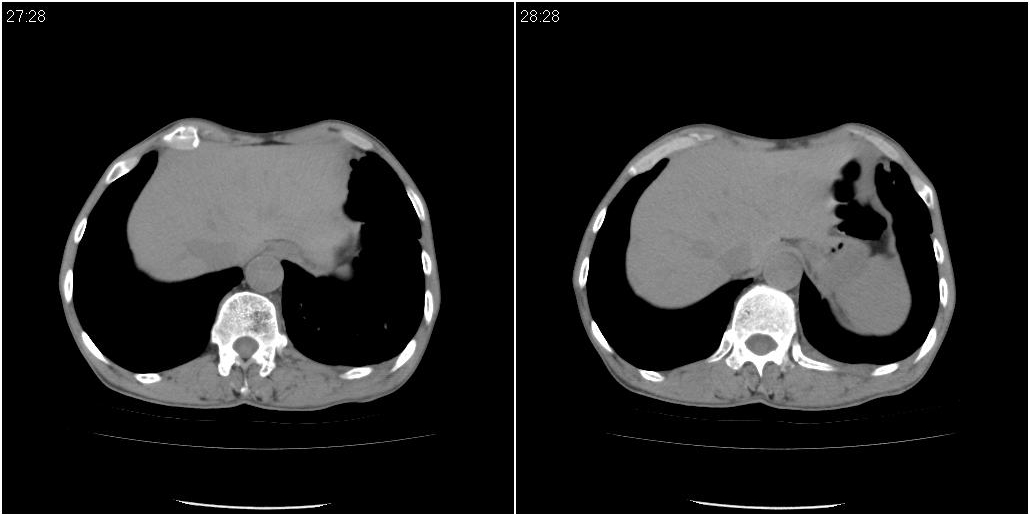

以下是ct检查的情况:

标题: ct增强: